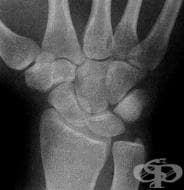

Мамографията е най-разпространеният метод за диагностика на млечните жлези. Представлява рентгенов м...